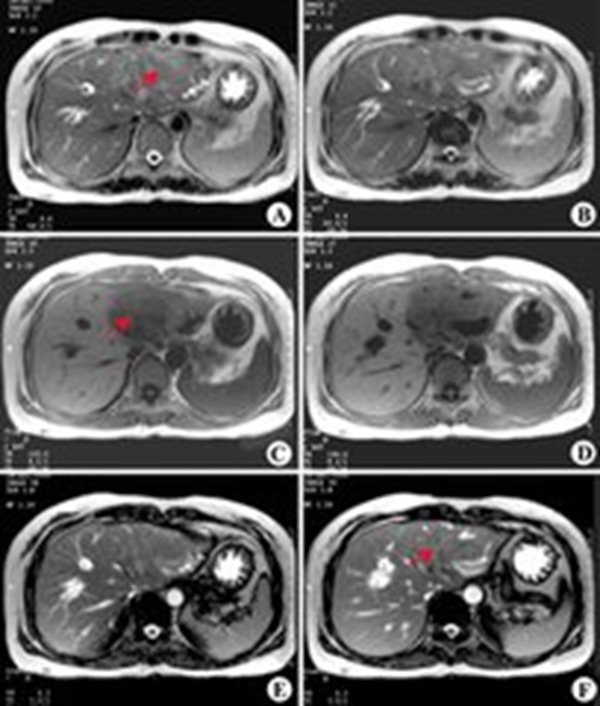

肝內膽管癌是指發生於肝內膽管(即左、右肝管第1級肝內分支以上)的癌腫,屬原發性肝癌的一種。

肝內膽管癌即從肝左右管合流部(肝門部)至末梢的膽管上皮細胞發生的癌。

組織學表現為腺樣分化或伴有粘液分泌,富於纖維性間質,比肝細胞癌硬。根據其發生部位分為末梢型膽管癌(肝內膽管瘤)及肝門部膽管癌。

臨床症狀因發生部位不同而異。末梢型膽管癌早期無症狀,晚期可有上腹不適、肝大、體重下降等;肝門部膽管癌常以黃疸為初發症狀。

ICC具有淋巴侵襲性,較易發生淋巴結轉移。 研究表明患者的1年、3年、5年生存率與手術當時腫瘤的分期、淋巴結轉移、血管侵犯、腫瘤的數目有關。

ICC術後複發率較高。血管侵犯、淋巴結轉移提示術後複發的可能性較大,而腫瘤大於5cm、腫瘤數目、血管侵犯以及周圍神經侵犯則提示容易早期複發。